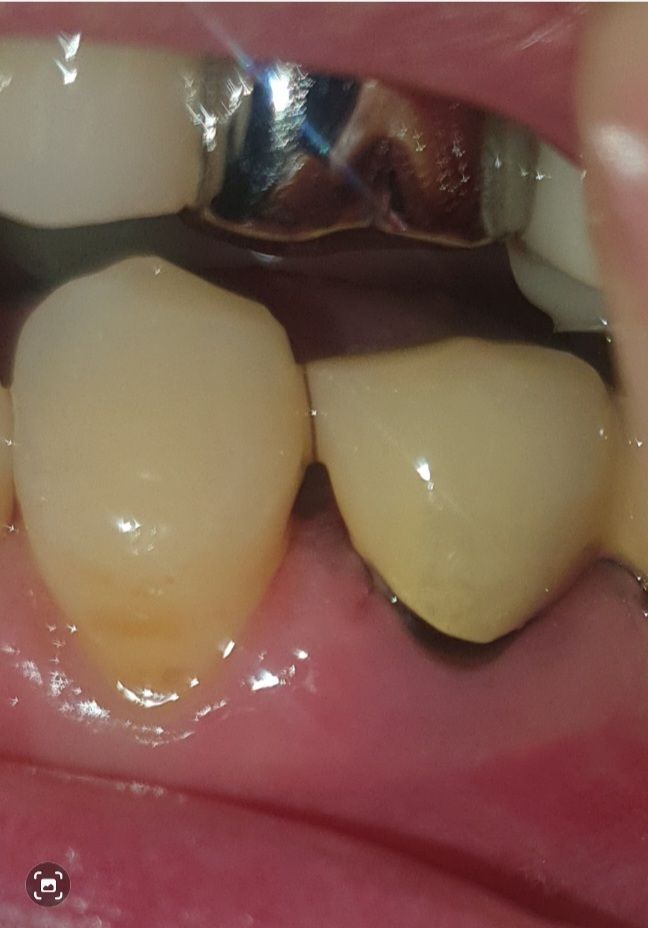

치주염 치과의사 선생님 계실까요~?

다름이 아니오라 예전에 신경치료후 크라운으로 덮어 씌웠습니다.

하지만 앞자연치아의 공간 사이와 크라운치아가 조금 벌어져있게 제작되었습니다.

그래서 저 사이의 공간이 좀 있는편이라 거기에 음식물 찌꺼기가 많이 끼는 편입니다.

이에 치실을 하루 한번 하는편인데, 잇몸이 조금 내려가는 기분이 들어서 이렇게 사진을 올리게 되었습니다.

혹시 치주염인지 봐주실 치과의사 선생님 계실까요..? ㅠㅠ..

• 3번 째 사진

해당 부위에서 출혈이나 농이 나온다면 치주염을 의심해볼 수 있습니다. 잇몸에 붓기 등은 있어보입니다.

보철물을 만들떄 무조건 치아 사이를 완전히 메꾸는건 아닙니다. 아마 처음에는 저정도 공간은 아니엿지만 시간이 지나면서 잇몸이 내려가면서 공간이 더 넓어진거 같습니다.

현재로써는 잇몸이 많이 내려와 있어보이지는 않으나, 이 공간이 음식물 찌꺼기로 인해 염증을 유발될수 있습니다.